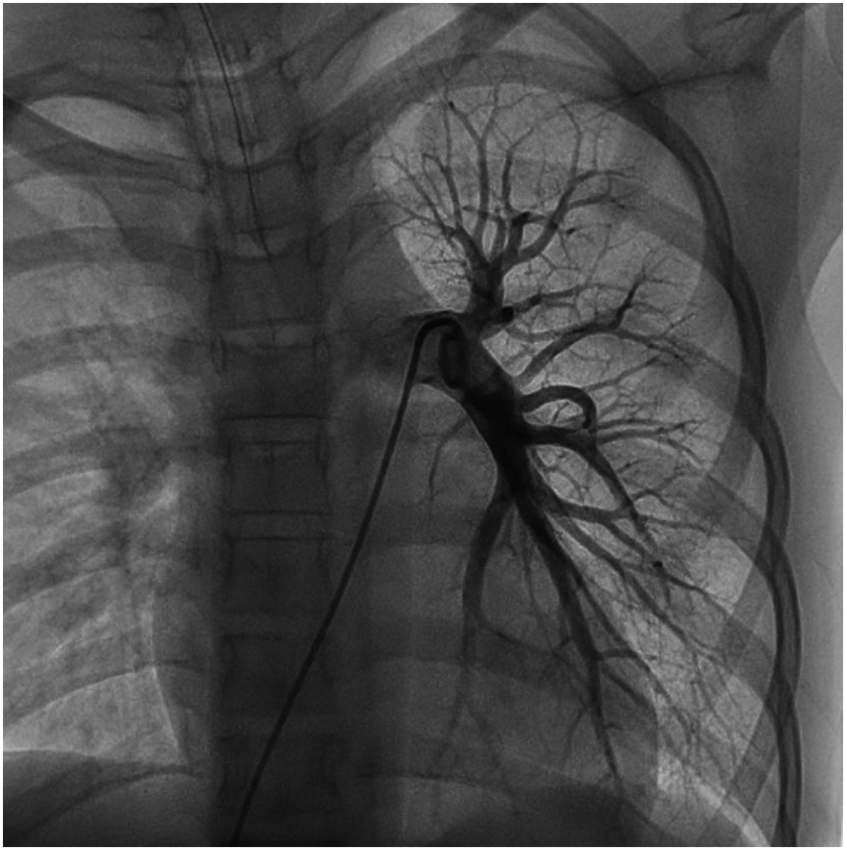

We performed a detailed evaluation of the cardiovascular system, including tests for right-to-left diverged heart disease, pulmonary arteriovenous fistula, severe valve regurgitation, and pulmonary hypertension.After conducting detailed echocardiography and cardiac CTA, we performed cardiac catheterization. The results of cardiac catheterization were negative. Cardiac catheterization findings are shown in Figures 3–6. We were unable to find a shunt at the atrial, ventricular, or aortic levels. The child's echocardiogram and cardiac macrovascular CT results were normal, ruling out complex congenital heart disease such as pulmonary atresia.

Figure 3

Frontal and lateral views of the child's left pulmonary arteriogram.

Figure 4